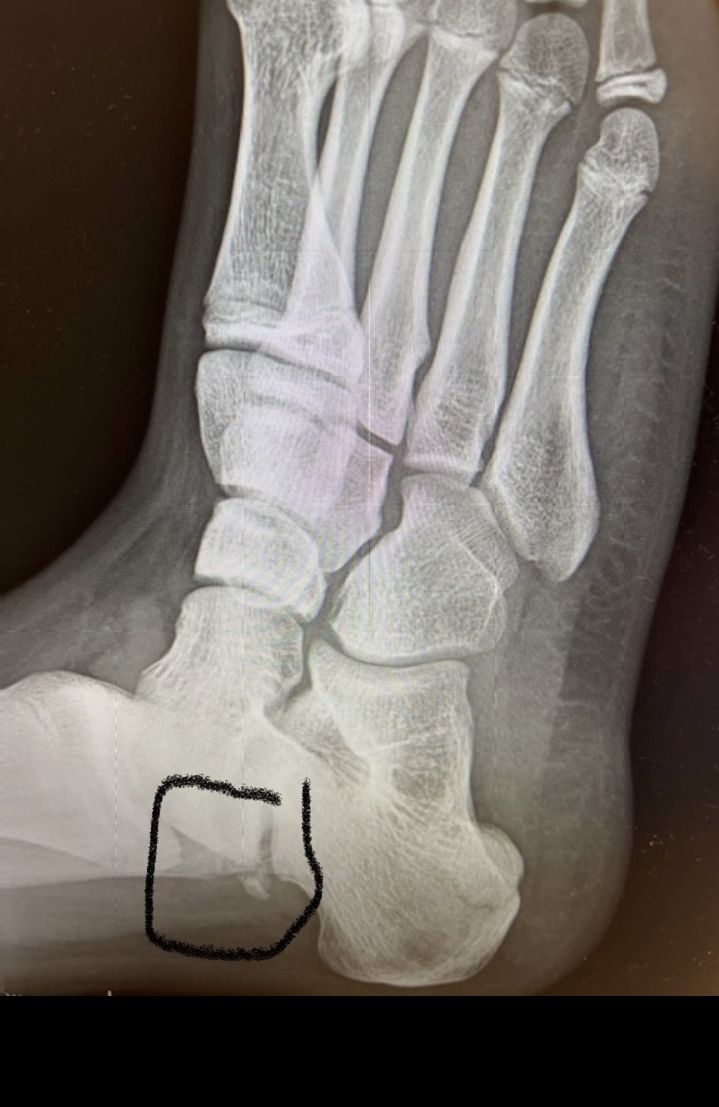

Hope you recover quickly!I broke my foot over the summer, which caused me to miss out on a lot of things. It was a case of my calf muscle, Achilles tendon, and one other muscle I forgot the name of actually rip a piece of bone off the back of my foot. I was in a cast for 2 weeks, and moved to a boot. I wore the boot for 6 weeks and got right back into my sports (I injured it while playing back to back soccer games). Turns out my tendons and muscles weren’t ready. I’ve been going to physical therapy for a while now. got the all clear to do some soccer drills. Super excited. Here’s an X-ray. It’s a crazy fracture.!View attachment 168390

Remind me of my friend who broke his patella. He broke it at a trampoline park, his tendons were so strong they tore it in half when he was going up for a dunk. (It was at SkyZone I’d any of you know what that is)Achilles tendon, and one other muscle I forgot the name of actually rip a piece of bone off the back of my foot.